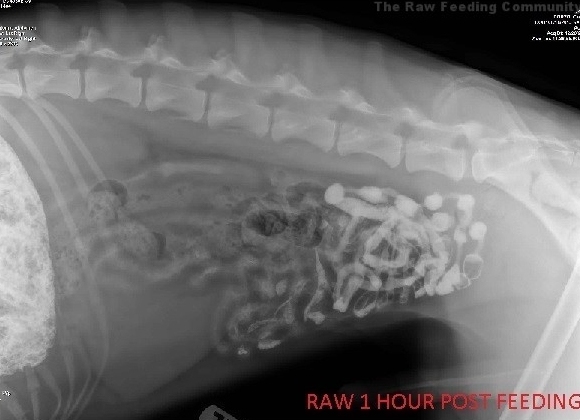

En 2015, la plus grande communauté Américaine, nommée Raw Feeding Community, a mené une expérience très intéressante. Elle a comparé le temps de digestion d'os charnus avec le temps de digestion de croquettes chez un chien. A l'aide de radiographies, on peut suivre l'évolution de ces différents aliments à travers le système digestif de l'animal.

Au bout de 30 minutes, les deux estomacs sont modérément distendus par la nourriture et le baryum. Avec le repas de croquettes (figure 1), la nourriture et le baryum se sont déposés dans le pylore au fond de l'estomac et se déplacent vers l'intestin grêle. La quantité de baryum passant dans l'intestin grêle avec le repas cru (figure 2) est négligeable car il y a probablement une grande portion de viande qui empêche le baryum de remplir tout l'estomac et de sortir.

Une heure après l'alimentation

Une heure après le repas, on peut voir que le diamètre de l'estomac commence à diminuer et que les intestins grêles se remplissent de baryum. Le mouvement de l'estomac vers l'intestin grêle est beaucoup plus spectaculaire avec les croquettes (figure 3) qu'avec le repas cru (figure 4). Dans les deux cas, on peut commencer à voir des matières fécales (non barytées) se former dans le gros intestin... des restes du repas précédent.